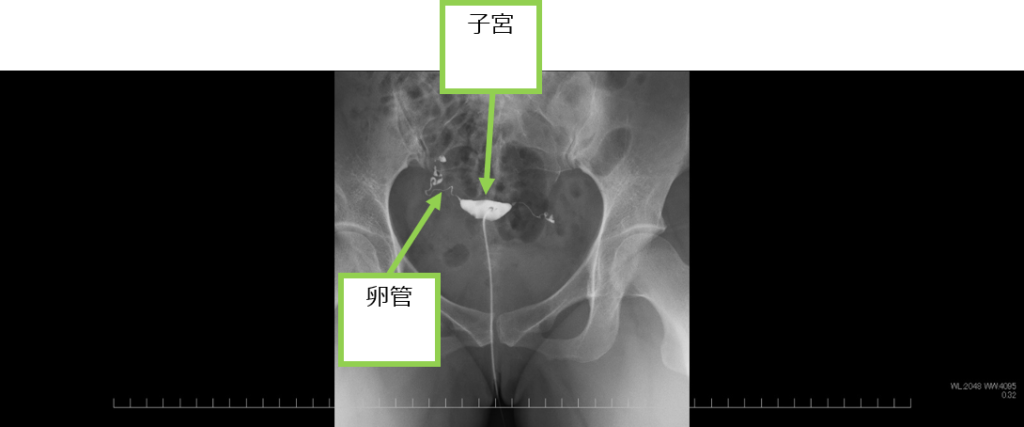

●子宮卵管造影

膣から子宮内に細いチューブを入れて油性造影剤(リピオドール)を注入し、子宮内の状態や卵管の通過性を評価します。検査は、産婦人科医師が担当します。産婦人科の看護師も付き添います。

子宮卵管造影

子宮の変形(奇形や筋腫など)がないか、卵管の通過性(狭窄や閉塞など)がないかを確認します。左図は子宮が正常な形をしており、左右の卵管の通過性も良いことが確認できます。